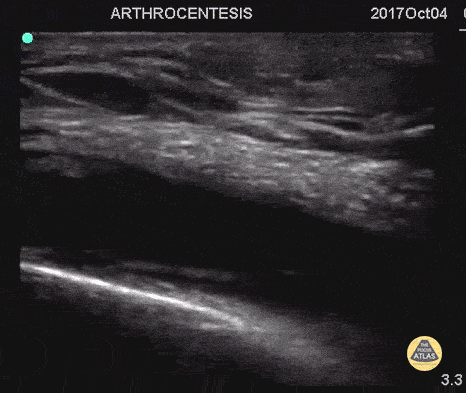

55 y/o with history of gout and osteoarthritis with an effusion. Join tapped and triamcinalone injected at the end. Going to tap a joint and unsure of the best spot? Grab POCUS to find the biggest fluid pocket. Many prefer the in-place US guidance technique for big targets such as a joint and watching the needle enter the whole way. Matthew Riscinti, MD - Kings County Emergency Medicine